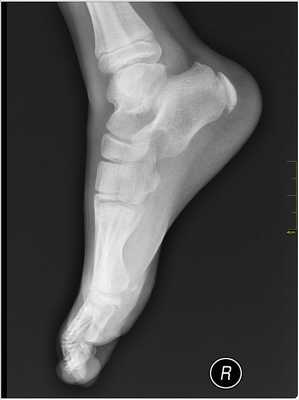

2. Рентгенография при болезни Севера:

• При рентгенографии изменения обычно отсутствуют

• Фрагментация и склерозирование апофиза заднего отростка пяточной кости достоверными признаками апофизита не являются:

о Могут быть обнаружены и у детей без клинической симптоматики

(Левый) Мальчик 12 лет. Выявлена клиническая симптоматика болезни Севера. При рентгенографии голеностопного сустава в боковой проекции определяются склерозированный и фрагментированный апофиз пяточной кости, а также зубчатый контур метафиза, что часто можно наблюдать и у детей без клинической симптоматики. Симптомы болезни Севера могут выявляться при тендинопатии ахиллова сухожилия, реакции апофиза на избыточную тягу ахиллова сухожилия или стресс-переломе пяточной кости.

Рентгенограммы в ранней стадии обычно неинформативны. Позже, однако, при сравнении со здоровой стороной можно определить фрагментацию эпифиза.

• Рентгенография не позволяет достоверно подтвердить наличие данного заболевания:

о Выполняется, чтобы исключить другие причины развития болевого синдрома в пяточной области

- Рентгенография: в большинстве случаев рентгеновские снимки оказываются бесполезными, поскольку очень часто у детей апофиз пяточной кости фрагментирован и плотен. Однако с помощью рентгена можно исключить другие травмы.